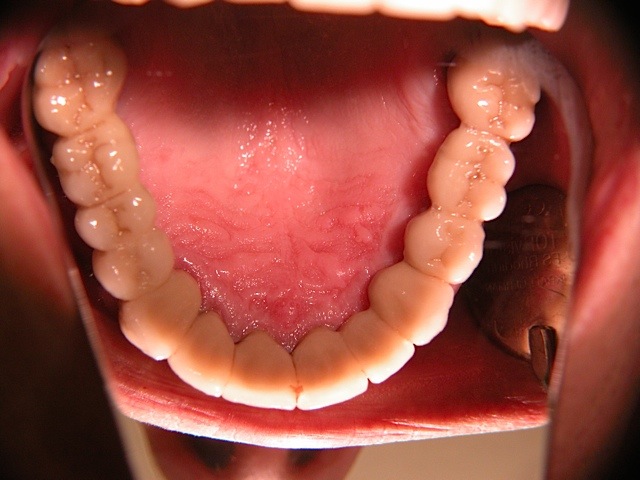

Die folgenden Patientenfälle sollen Ihnen einen Einblick in die Möglichkeiten der modernen Implantation geben.